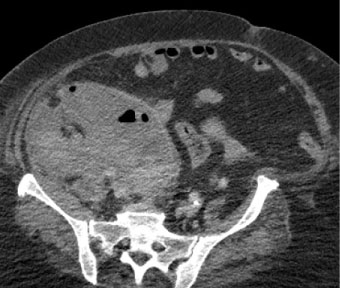

Anticoagulation was started with subcutaneous Heparin but this should be discontinued due to the patient developed severe hypotension, paleness and abdominal pain. Severe anemia was shown in blood analysis. The patient was diagnosed with a large hematoma on psoas, oblique muscles and peritoneal cavity that displaces the right kidney in the anterior way, bladder and uterus (Figure 1). Embolization was performed with minicoils to L3 lumbar artery showing active bleeding.

Figure 1: Large hematoma on psoas, oblique muscles and peritoneal cavity that displaces the right kidney in the anterior way, bladder and uterus. View Figure 1